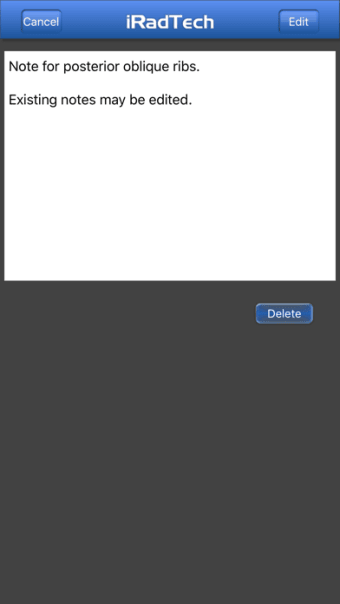

Un'applicazione versione completa per iPhone, di Ballinger e Bruckner LLP.

IRadTechè un programma completo per iPhone, che fa parte della categoria 'Medicina'.

IRadTech funziona su iOS 12.1.2 e versioni successive. La versione attuale dell'app è 4.0.1 e puoi eseguirla solo in inglese.